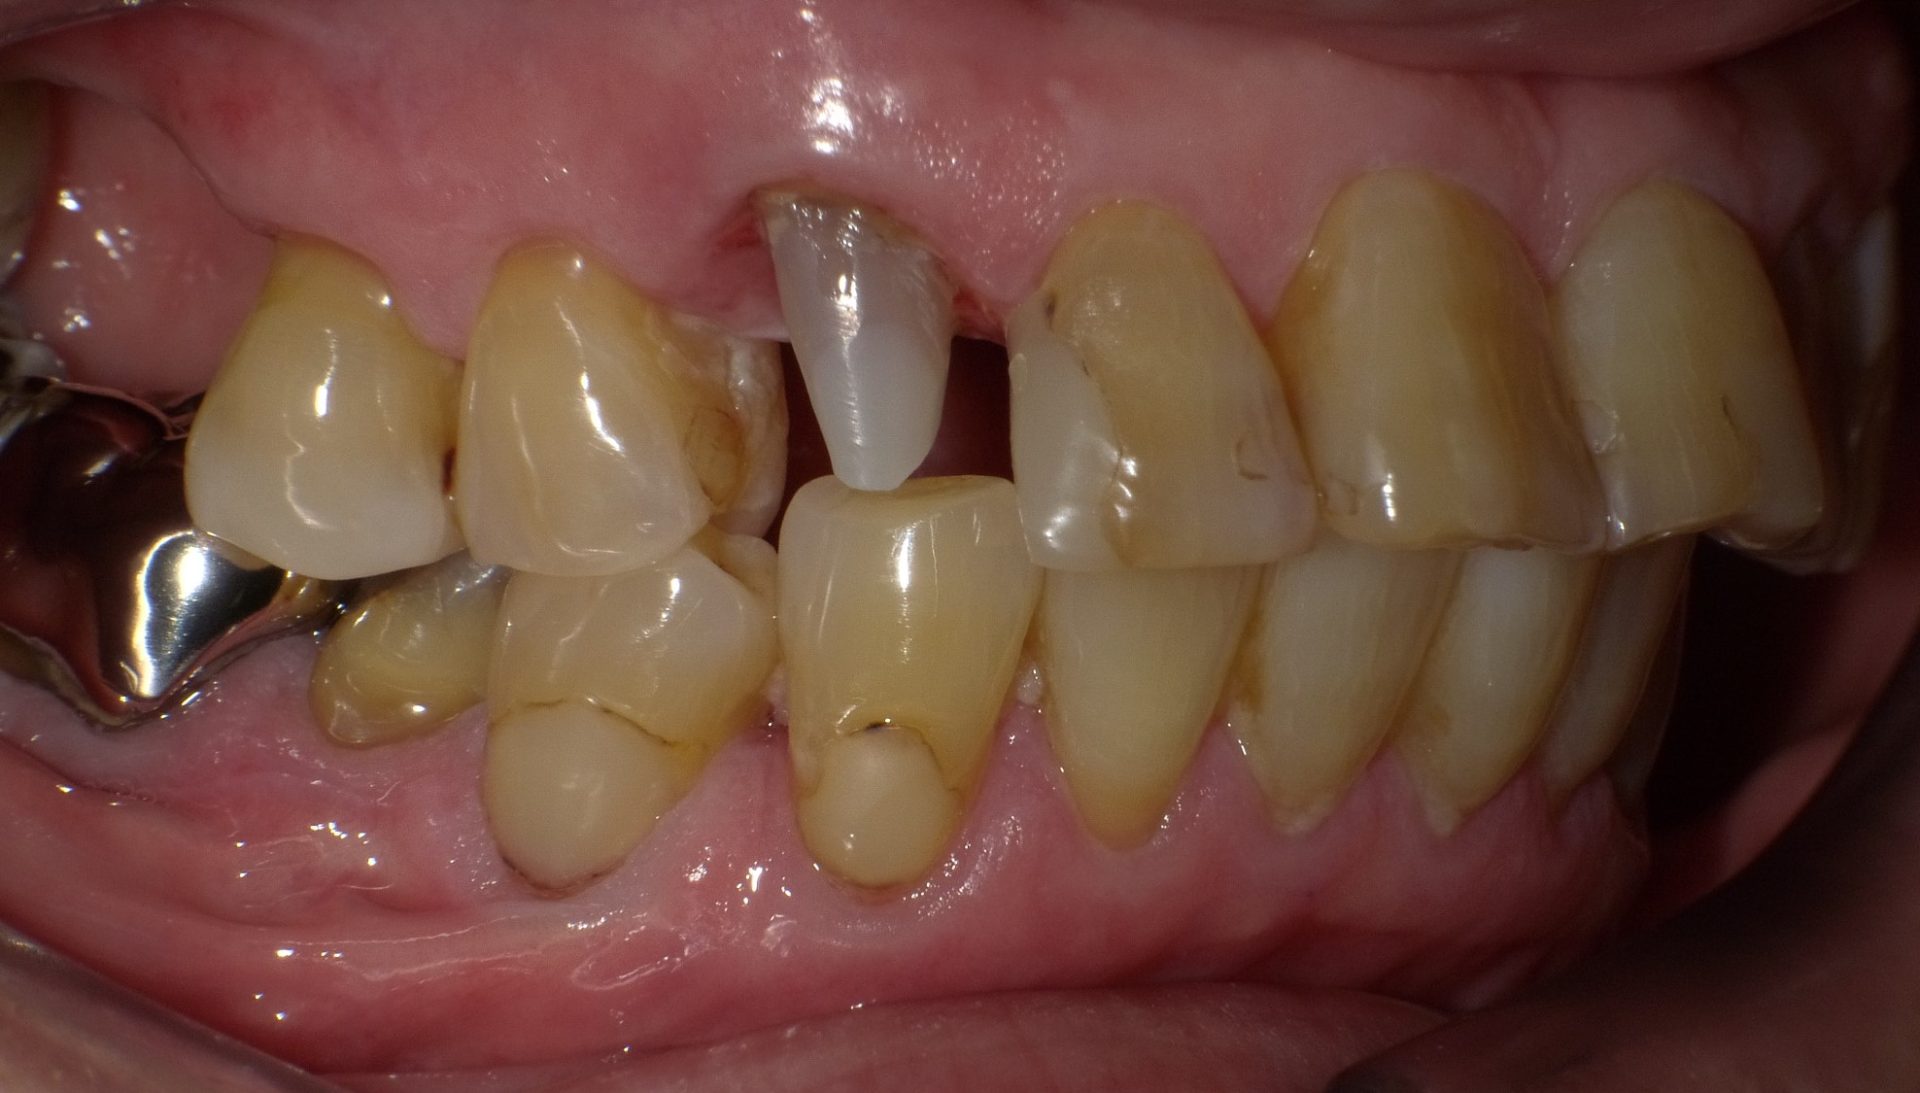

全周1mm程度、一回り小さく削った歯の上にセラミックで作った被せをすっぽり被せ、歯の色や形、歯並びなどをトータルに改善する方法です。セラミッククラウンは、歯を削ることで、表現や修飾の自由度が大きくなり、天然歯と同様あるいはそれ以上に見事な色合いや質感が出せるため、審美的効果が高い治療法です。

虫歯が大きく、その部分を取り除いたあと歯が少ししか残らない場合などにこの治療法を用います。歯にセラミックの冠を被せますので、ラミネートべニアより歯の形や大きさ、色調ともに表現の自由度が格段に広がりますが、歯を削る量は、それだけ多くなります。